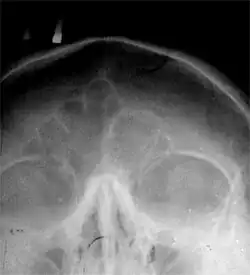

Ло́бная кость (лат. os frontale) — непарная кость мозгового отдела черепа; участвует в образовании переднего отдела свода черепа и передней черепной ямки его основания. Она состоит из четырёх частей: вертикально расположенной чешуи (лат. squama), двух горизонтальных глазничных частей (лат. pars orbitalis) и дугообразной носовой части (лат. pars nasalis)[1].

Наружная поверхность (лат. facies externa) чешуи лобной кости гладкая, выпуклая, имеет в нижней части срединной линии небольшое возвышение, соответствующее остаткам лобного шва, который в детстве разделял лобную кость надвое. С каждой стороны от шва примерно в 3 см от надглазничного края располагается округлое возвышение — лобный бугор (лат. tuber frontalis). Здесь появляется первичная точка окостенения лобной кости. Размер и форма лобных бугров индивидуальны; на детском черепе они выделяются сильнее и иногда могут быть асимметричными, у мужчин бугры больше, крупнее, чем у женщин. Кость здесь имеет гладкую поверхность и покрыта сухожильным шлемом.

Ниже каждого лобного бугра выступает дугообразное возвышение — надбровная дуга (лат. arcus superciliaris); между и немного выше выпуклостей надбровных дуг лобная поверхность имеет вид углублённой площадки — надпереносье, или глабелла (лат. glabella). Обычно у мужчин надбровные дуги также выделяются сильнее, и степень их выстояния зависит от размеров лобных воздухоносных пазух.